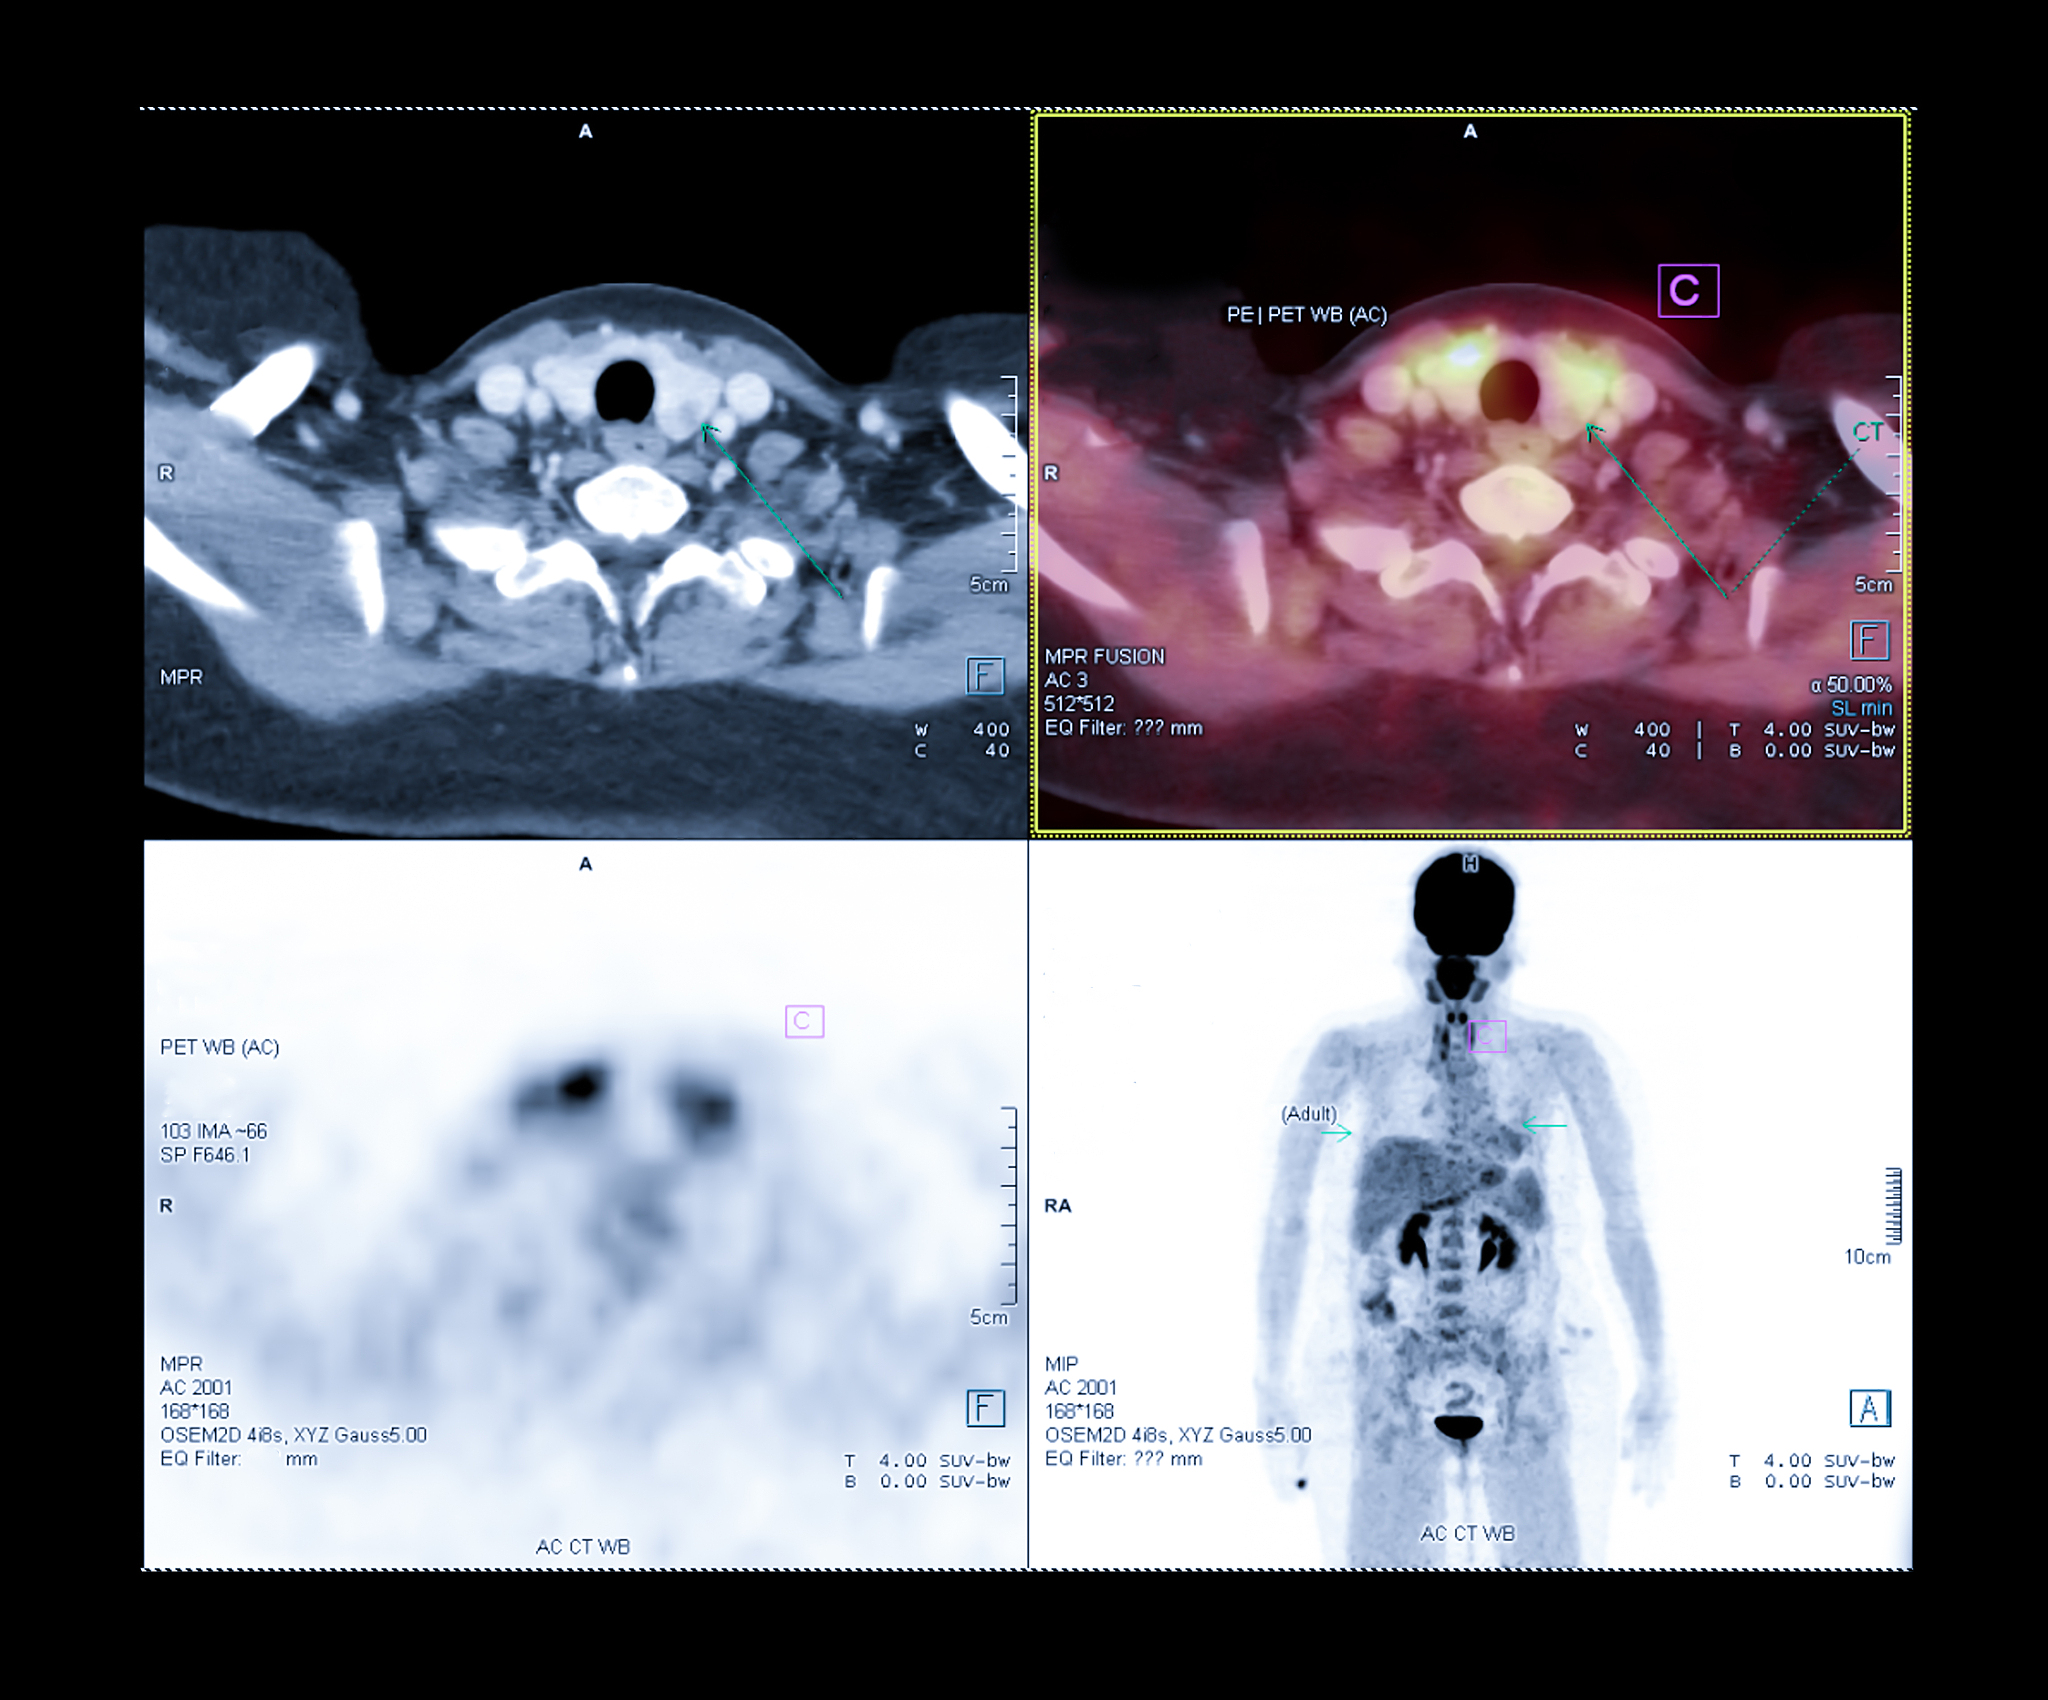

肺部肿瘤的结节复查是否增大取决于其直径的变化。一般情况下,如果结节的直径在两次检查中增加了3毫米以上,则可以判定为结节增大。但是,肺部结节增大并不一定表示肿瘤恶化,可能也是由于其他因素引起的,如炎症或感染。因此,如果肺部结节有增大的趋势,通常需要进一步的评估和检查,如CT扫描、PET-CT、活检等,以确定其性质和进一步治疗计划。建议咨询专业医生进行详细的诊断和治疗建议。